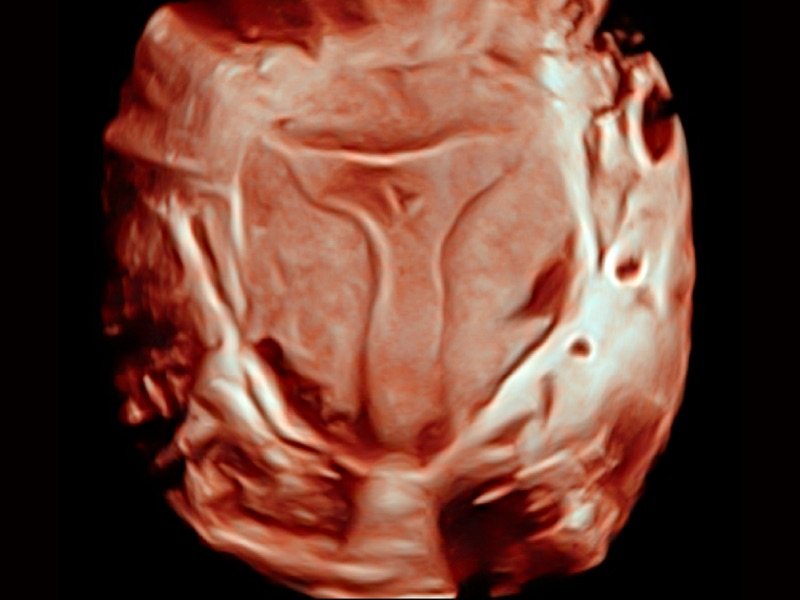

S-Live Silhouette

Durch den Einsatz einer virtuellen Lichtquelle und des Schattierungseffekts sieht S-Live Silhouette durch die Oberfläche hindurch und bildet die Umrisse von Knochen, Organen, Hohlräumen, Gefäßwänden und anderen inneren Strukturen scharf ab. Diese Funktion eignet sich hervorragend zur Erkennung der normalen Anatomie und zur Diagnose komplexer angeborener Fehlbildungen.